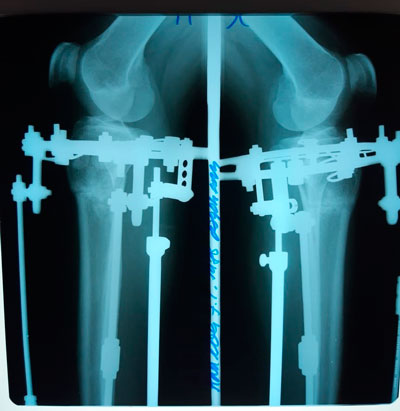

Исходник - 34 года.

Варусная деформация голеней.

Ротация с обеих сторон.

Дата операции - 20.03.2019г.

перед крутками